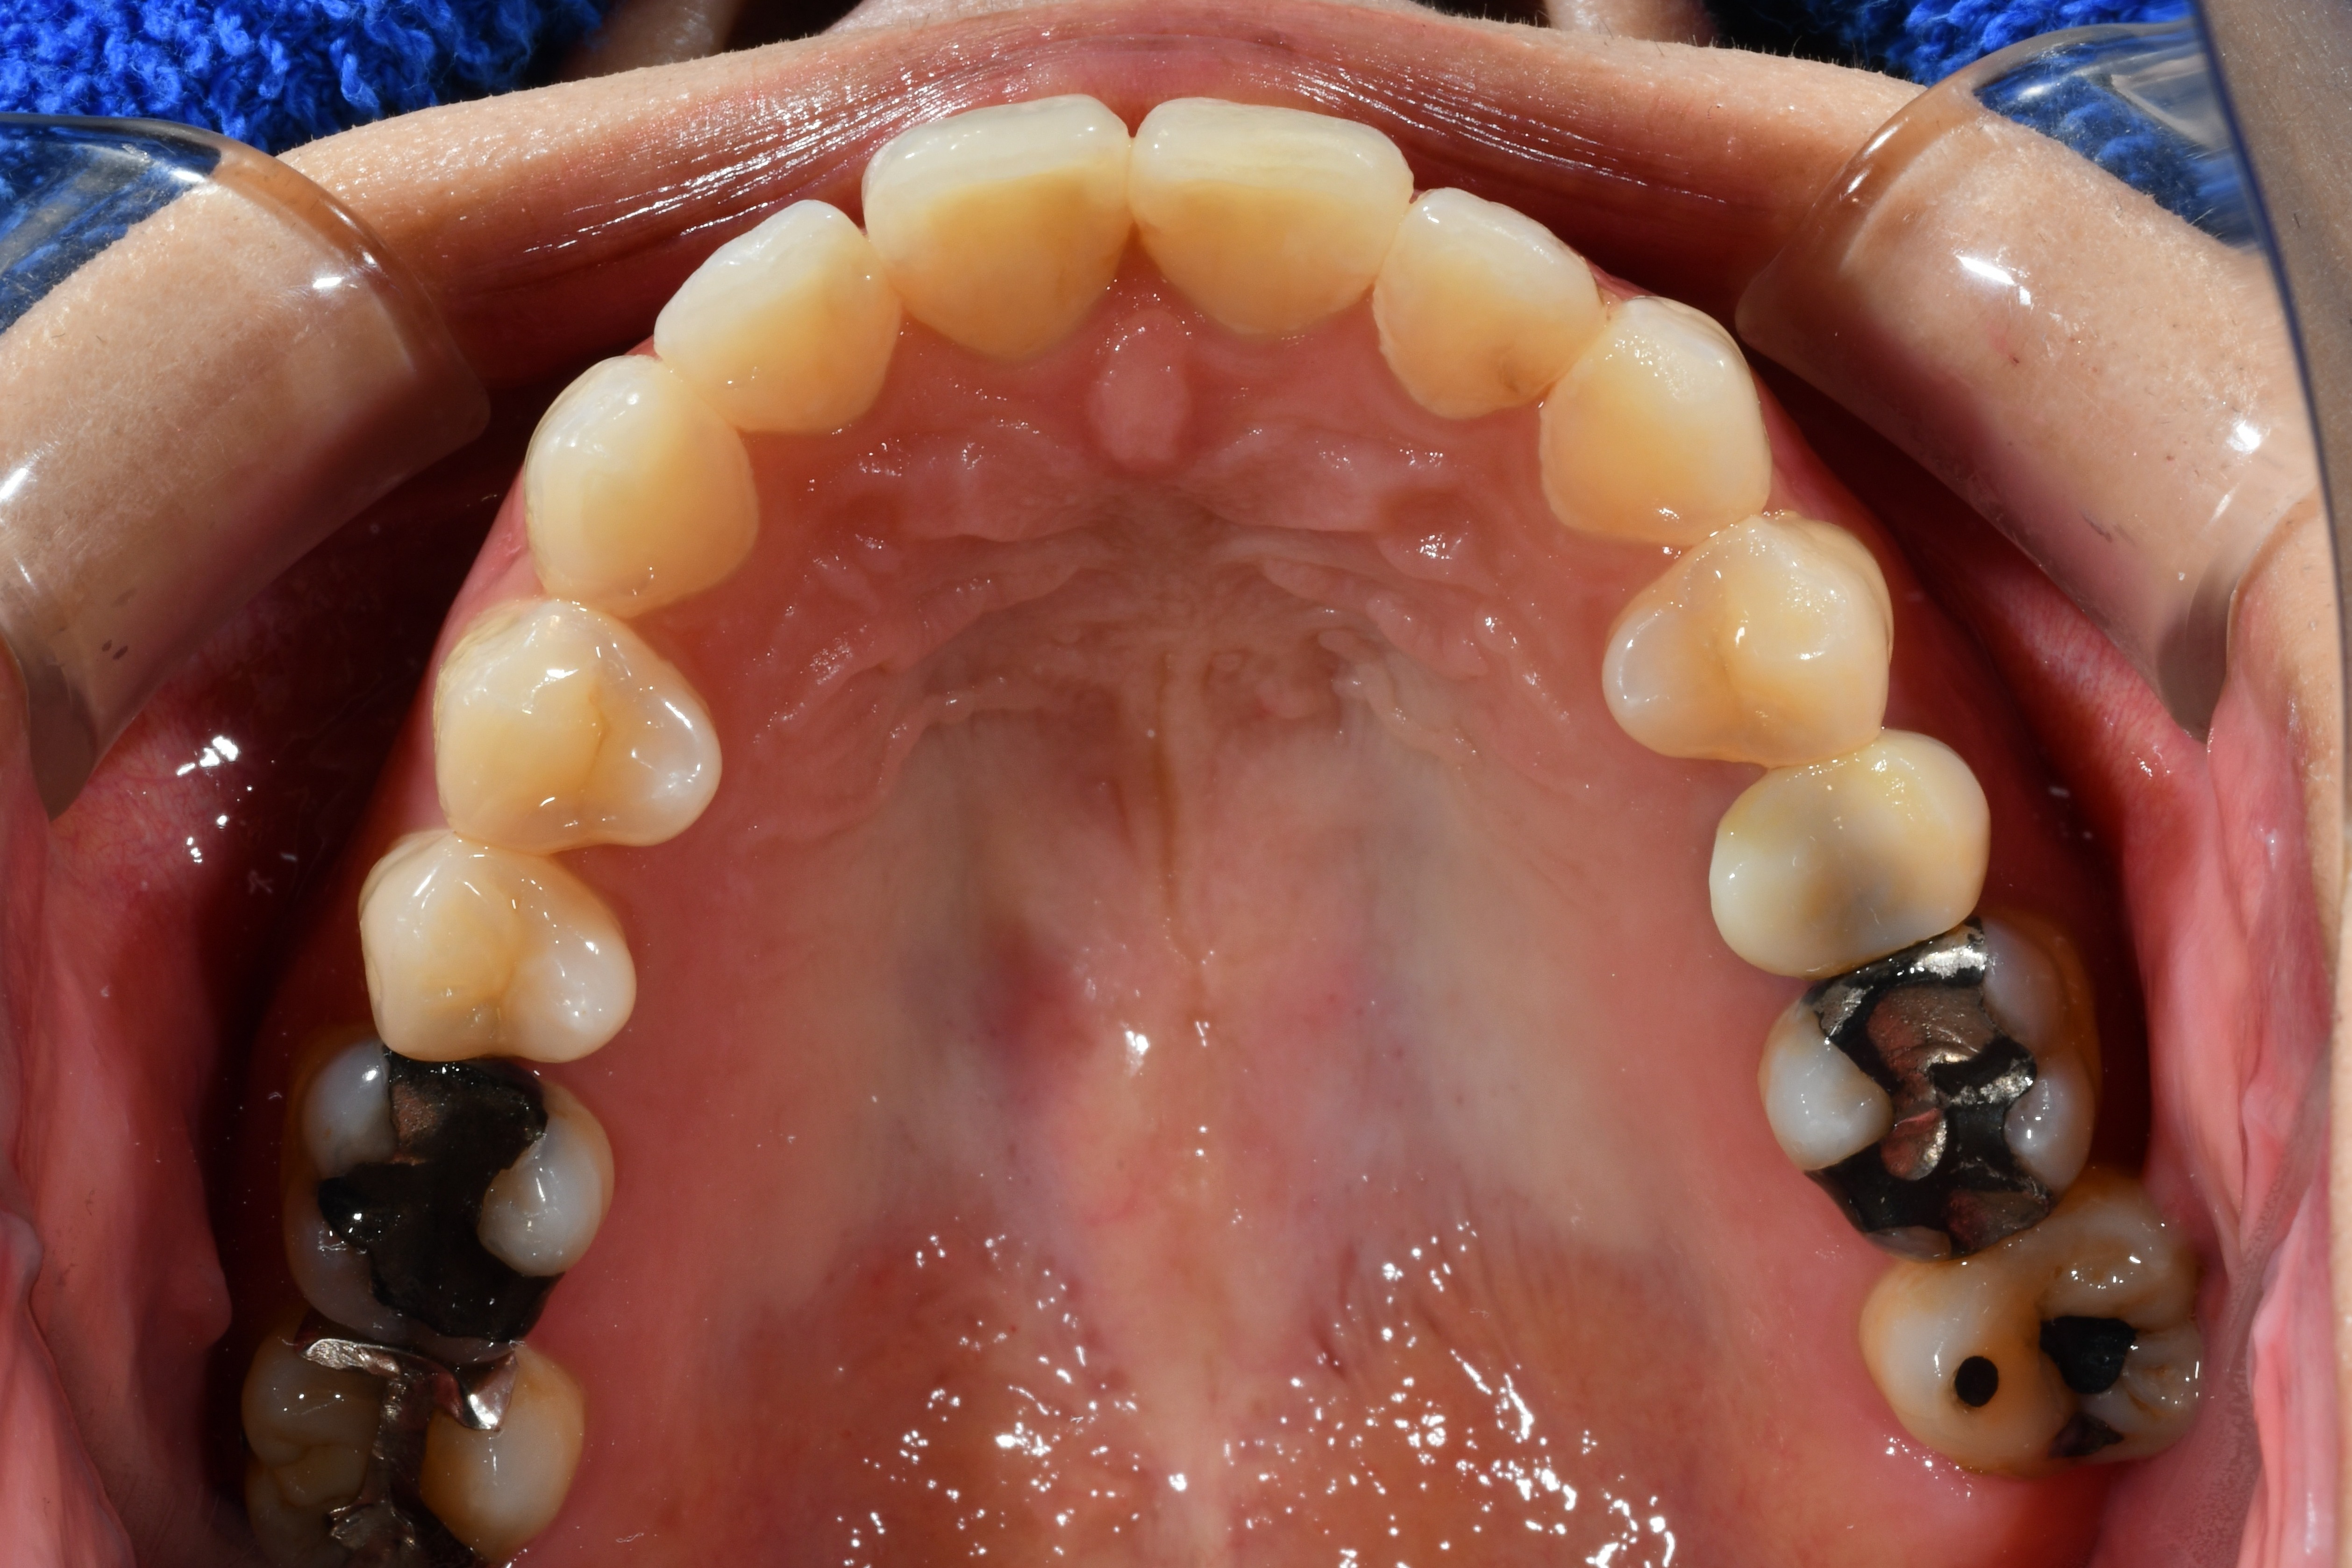

毎週自分で歯並びの写真を撮っていたので日々綺麗になっていく歯並びを見るのが嬉しく、家族からも綺麗になったねと言われました! マウスピース矯正と並行してホワイトニングも行っていたので、歯が格段に綺麗になるのを実感できたのが嬉しかったです。

| 治療内容 | マウスピースを用いた歯列矯正 |

| 追加処置 | IPR |